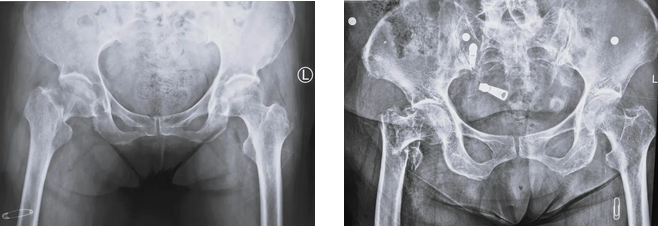

常见的老年髋部骨折有股骨颈骨折(左图)和股骨粗隆间骨折(右图)